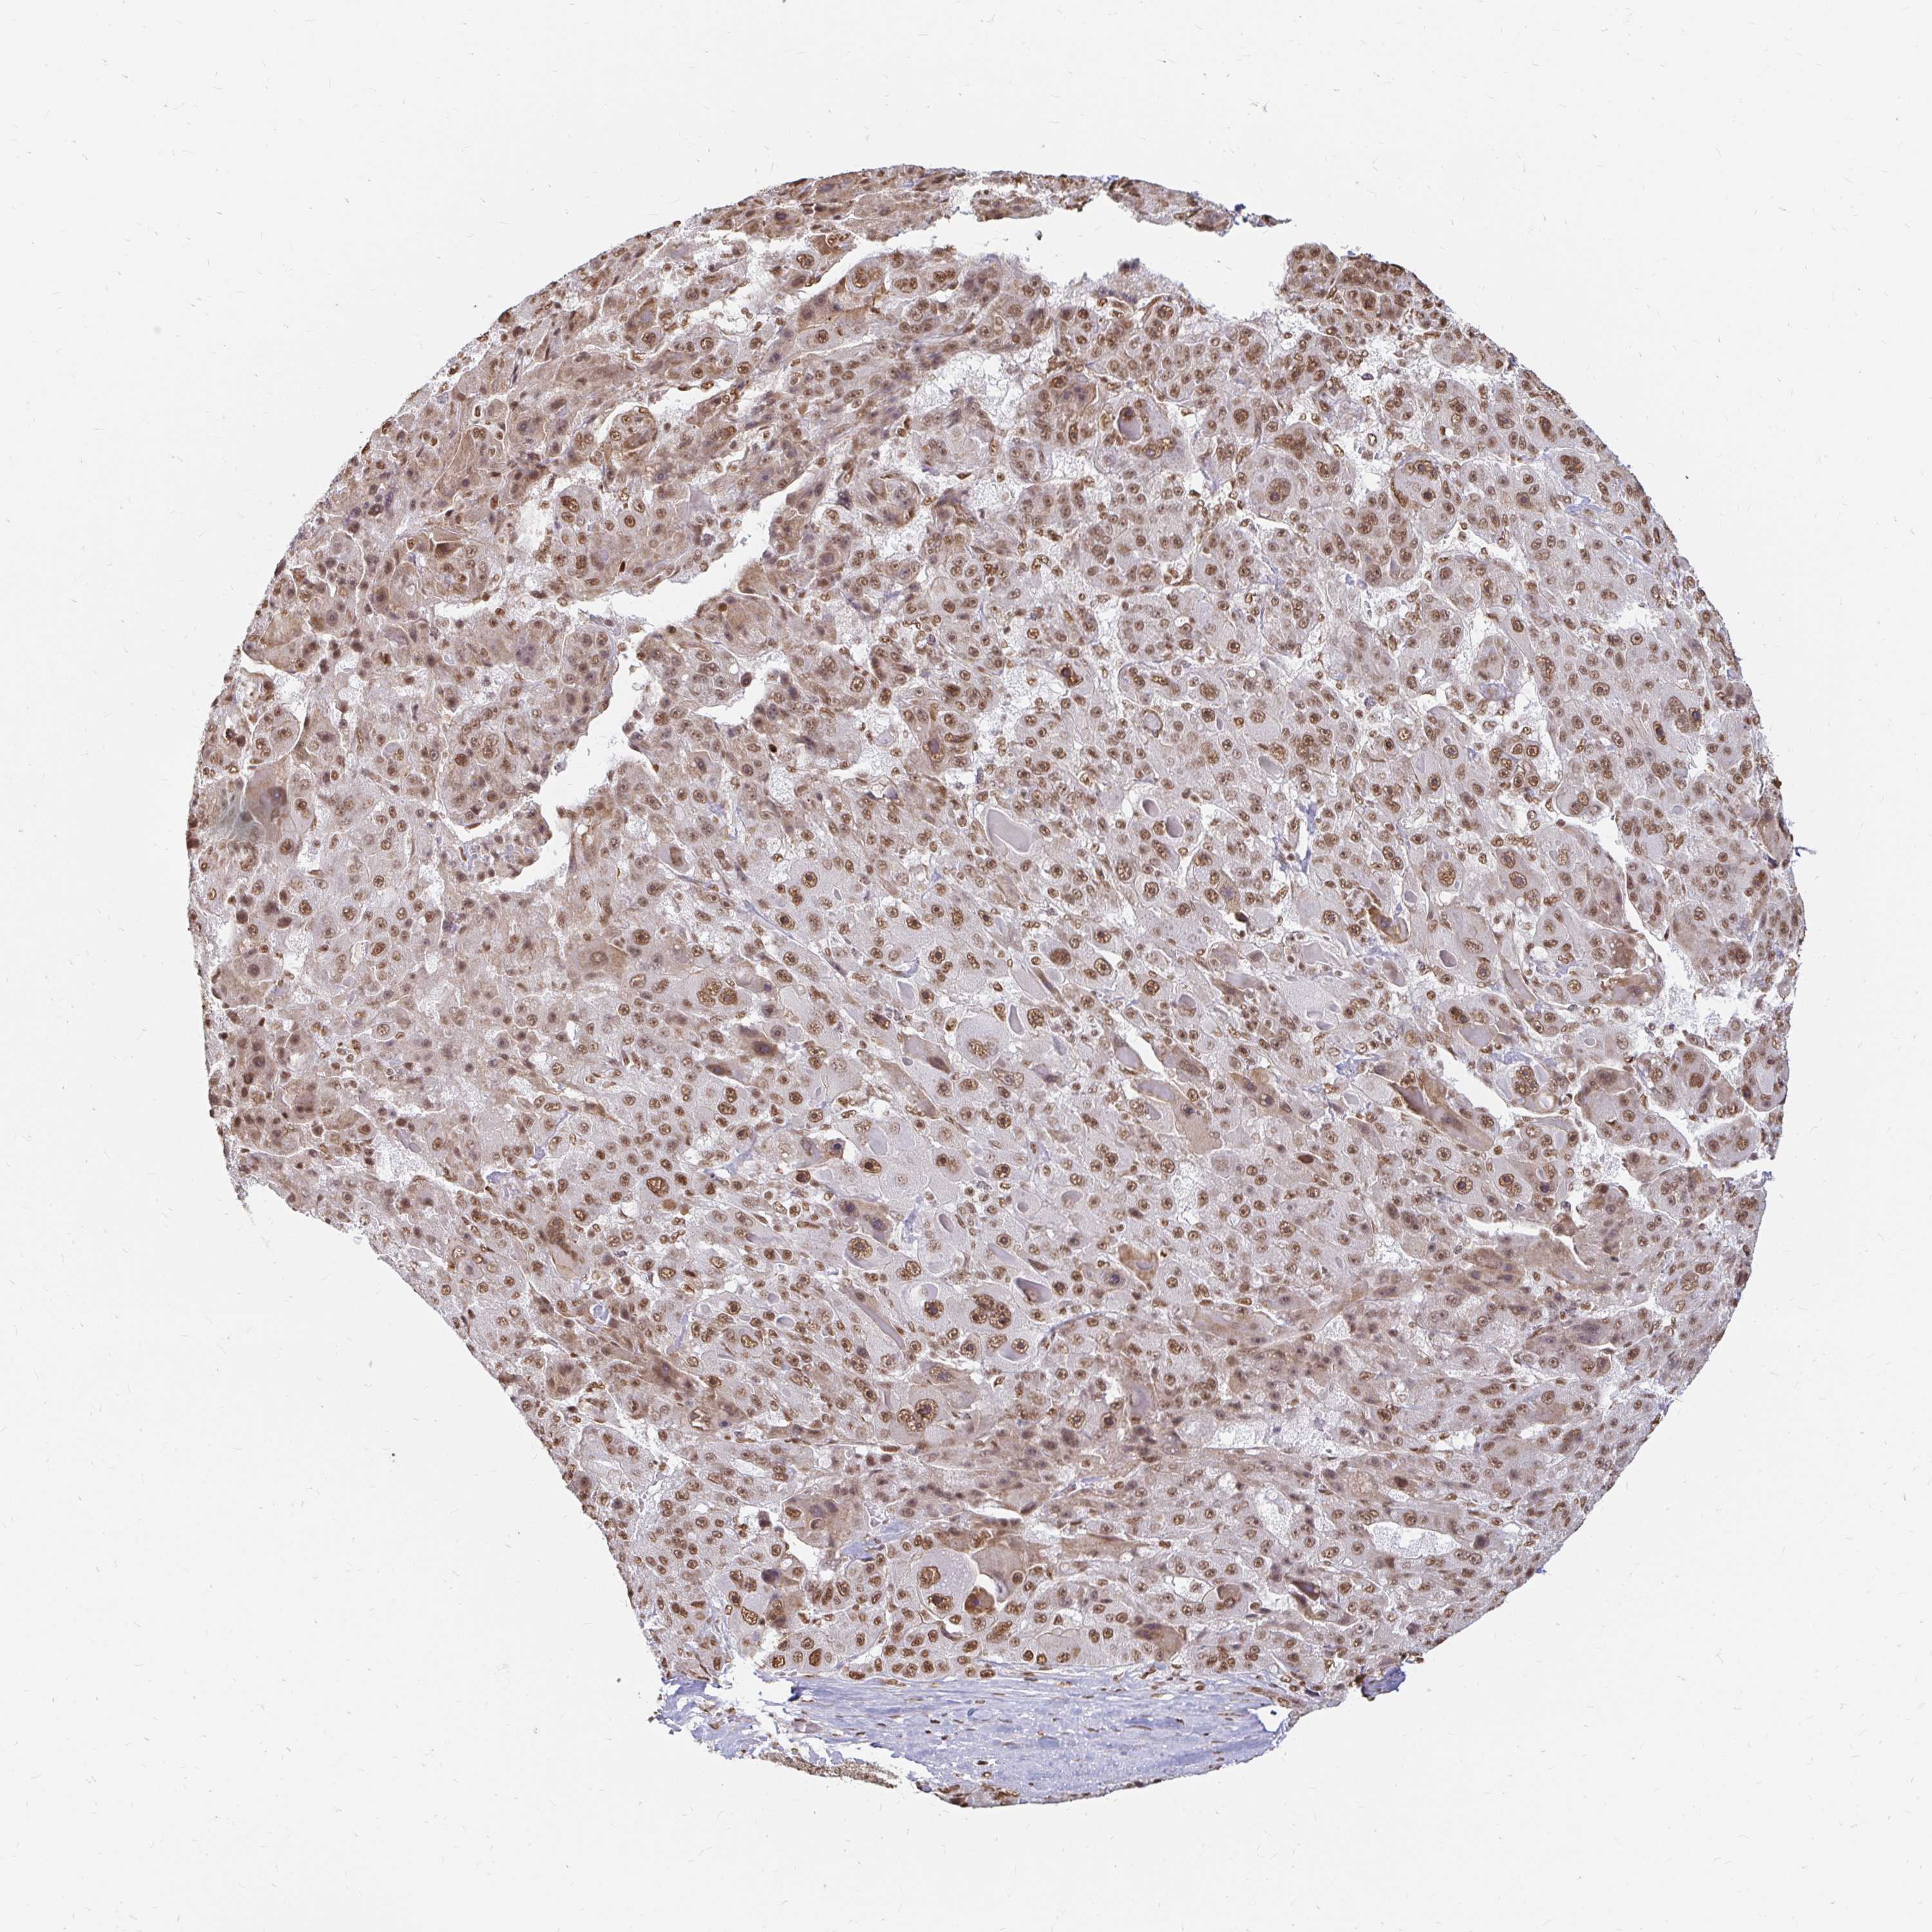

LIVER CANCER - Protein expressioni

A mouse-over function shows sample information and annotation data. Click on an image to view it in a full screen mode. Samples can be filtered based on level of antibody staining by selecting one or several of the following categories: high, medium, low and not detected. The assay and annotation is described here.

Note that samples used for immunohistochemistry by the Human Protein Atlas do not correspond to samples in the TCGA dataset.

Antibody stainingi

Antibody staining in the annotated cell types in the current human tissue is reported as not detected, low, medium, or high, based on conventional immunohistochemistry profiling in selected tissues. This score is based on the combination of the staining intensity and fraction of stained cells.

Each image is clickable and will lead to virtual microscopy that enables deeper exploration of all samples and also displays staining intensity scores, fraction scores and subcellular localization as well as patient and tissue information for each sample.

Antibody HPA041057

Antibody HPA058707

Antibody CAB011532

Staining

High

Medium

Low

Not detected

Intensity

Strong

Moderate

Weak

Negative

Quantity

>75%

75%-25%

<25%

None

Location

Nuclear

Cytoplasmic/membranous

Cytoplasmic/membranous,nuclear

Cholangiocarcinoma

Carcinoma, Hepatocellular, NOS